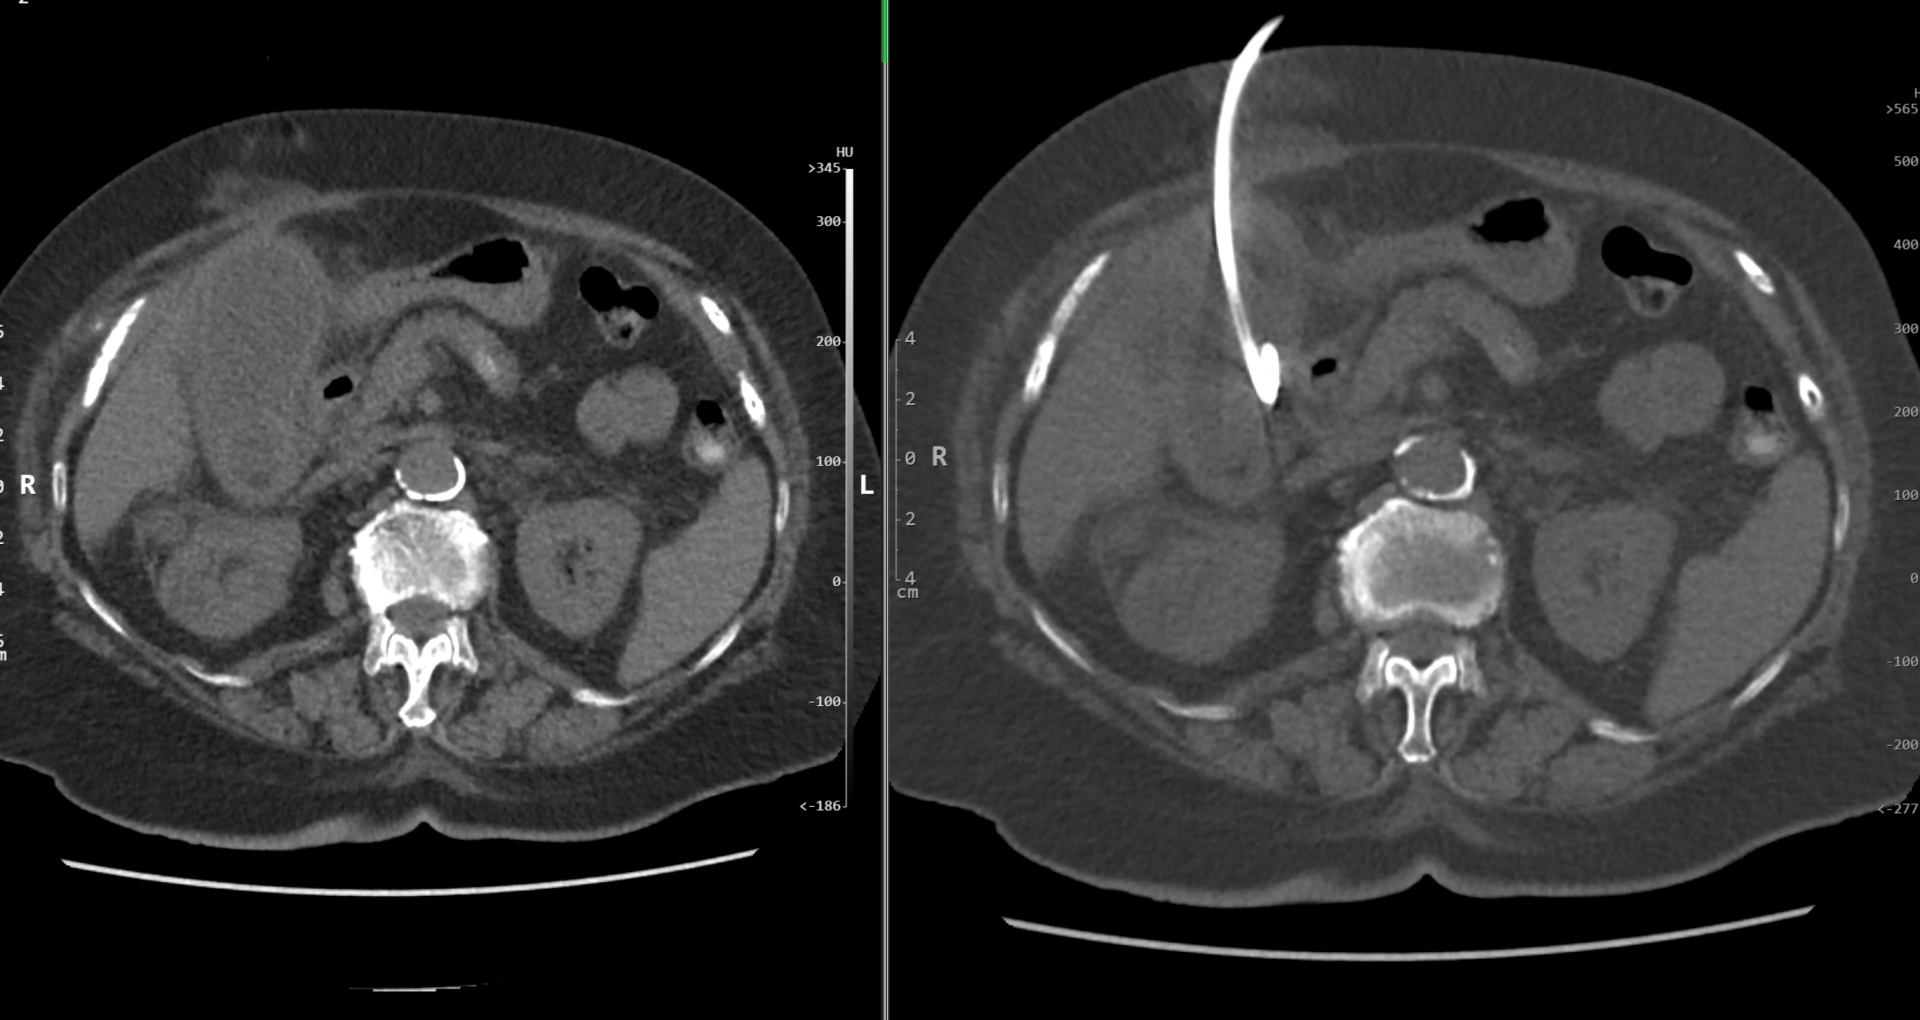

Perkutánní biopsie a drenáž tekutinové kolekce pod kontrolou CT

Perkutánní biopsie (drenáž) pod kontrolou CT (počítačové tomografie) je definována jako cílené umístění speciální bioptické jehly nebo drénu do chorobného ložiska za účelem odběru tkáně, buněk či tekutiny pro další šetření.

Perkutánní biopsie je diagnostický výkon – odběr vzorku tkáně z chorobného ložiska. Je nutná pro přesnější určení povahy chorobného procesu, ze kterého byl vzorek odebrán, je nutná pro stanovení dalších léčebných postupů. Často rozhodne, zda-li se jedná o zhoubný či nezhoubný proces a umožní usměrnit další léčení.

Perkutánní drenáž je zavedení tenké trubice (drénu) do kolekce tekutiny v těle. Jedná se o výkon léčebný i diagnostický. Dutina s tekutinou je při drenáži vypuštěna, odebraná tekutina je odeslána k rozboru.

Co se vlastně při biopsii odehrává?

Na vyšetřovně, kde se bude výkon provádět je pacient uložen do polohy umožňující nejlepší přístup k ložisku. V této poloze musí po dobu výkonu pokud možno bez pohybu setrvat. Lékař provádějící výkon zaměří přístrojem ložisko, určí nejbezpečnější přístup, provede místní znecitlivění místa vpichu, zavede bioptickou jehlu, provede odběr vzorků. Poté jehlu odstraní a místo vpichu převáže.